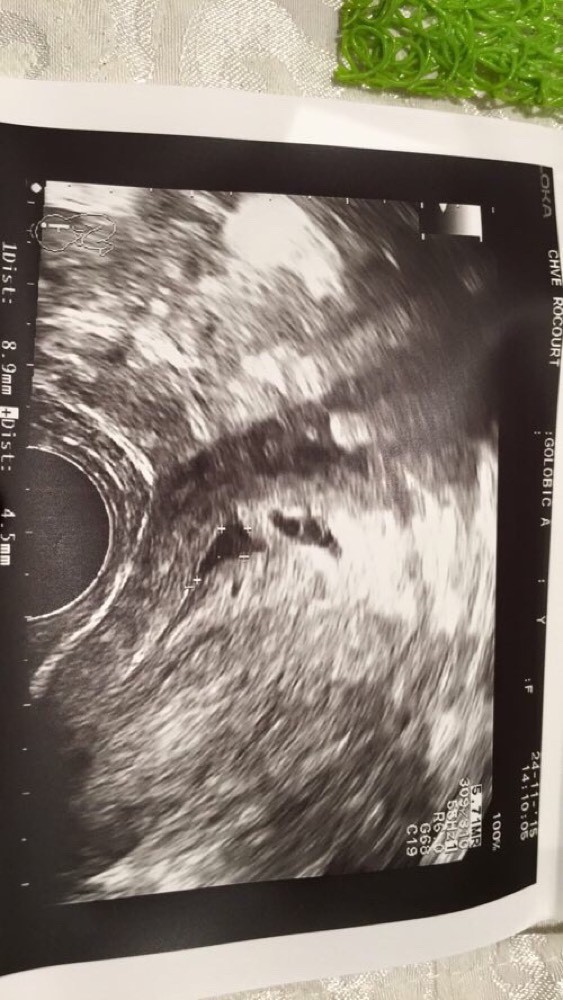

Echographie bebe 2 semaines- Bonjour, j'ai fait ma première écho morpho a 12 SA 6 jours et on me dit fille à 80% à confirmer avec une sage femme ( comme mon gynécologue non obstétricien) et 2 semaines apres Rdv avec mon gynécologue qui me dit garçon 😰 je ne sais J'en suis à 3 Sg 2 ( soit 23 dpo ) et j'ai fait une echographie ce matin Mau taux hcg était à 21 dpo de 3544 ui Alors à l'echo gygy a trouvé un sac ovulaire de 10 mm, avec un tt petit point dedans ( elle a dit c sans doute le futur embryon mais pas ure )

À semaines Les mouvements du fœtus deviennent clairement perceptibles par la maman, pas toujours pour le papa qui doit attendre pour cela encore 1 à 2 semaines A ce stade, le fœtus a déjà des phases de sommeil bien marquées, alternées entre des périodes d'activité et d'immobilité 1ère échographie à 2 semaines Rejouer 1 ère échographie à 4 SA et 4 jours l'oeuf est visible sous la forme d'une petite vésicule mesurant 3 mm de diamètre et entourée d'un halo La deuxième échographie a lieu entre la 22e et 24e semaine d'aménorrhée, soit à la fin du 5e mois de grossesse Réalisé par un échographiste, cet examen dure entre 30 et 45 minutes Le médecin commence par appliquer un gel transparent sur votre ventre afin de faciliter le passage des ultrasons

Ecographie a deux semaine bonjour, je suis egelement enceinte de deux semaine mercredi 5 AOUT le gyneco ma fait une echo (par rapport a mes derniere regle il pensait que jetait enceinte de 1 MOISUn embryon, premier signe de vie visible Il s'agit parfois d'un14 semaines de grossesse / 16 SA Guide ;